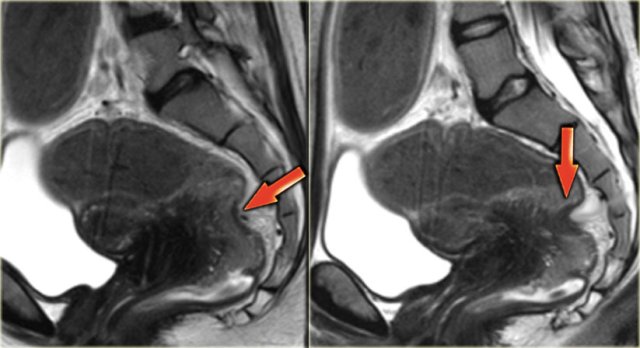

This sagittal T2-image shows deep infiltrating endometriosis in the posterior cul-de-sac with infiltration of the rectal wall.

The T2-images demonstrate two fan-shaped hypointense lesions (red arrows).

These findings are typical for endometriotic lesions infiltrating the muscular layer of the bowel wall.

There is also some submucosal swelling, seen as hyperintensity on the luminal side of the bowel wall.